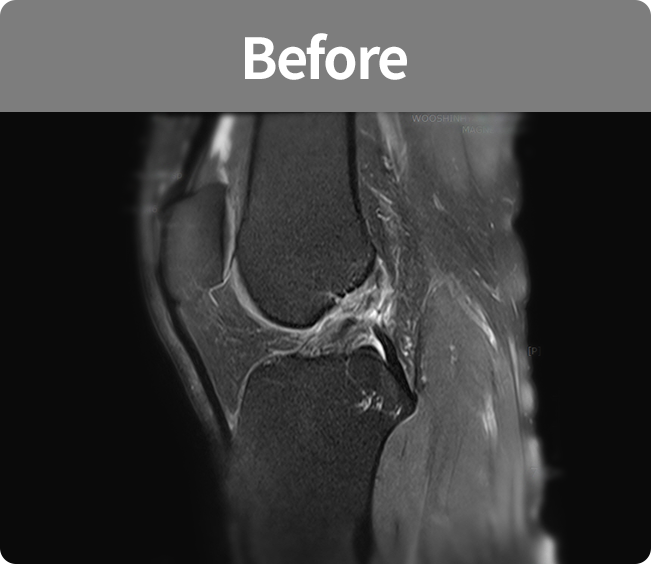

관절경 수술

MRI나 CT에서 보이지 않는 병변을 약 1㎝ 내외의 구멍을 내서 관절내시경 기구를 통하여

모니터를 이용하여 정확한 관절 질환의 검사하며, 파열된 힘줄 및 연골판을 봉합하거나,

미세 천공술을 시행하여 연골의 재생을 촉진시키는 수술법

(반월상연골판 부분절제술, 반월상연골판 봉합술, 반월상연골판 이식술, 무릎연골 미세천공술)